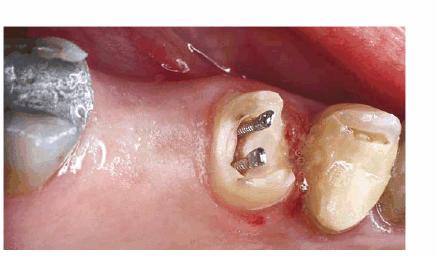

Sequence of Treatment for Posterior

Teeth (Molars and Large Premolars)

The core build-up for a posterior tooth should be placed prior to crown

preparation. A sufficient amount of time should have elapsed since completion

of the root canal therapy to be confident that it has been successful. The

tooth should be asymptomatic and not sensitive to percussion. Following root

canal therapy, the typical molar will have a large existing restoration. All

restorative materials and caries should be removed. The gutta-percha should be

removed from the pulp chamber. The gutta-percha can be removed 1 to 2 mm into

the canal orifices to increase retention (Figur 323s1823d e 18-11). If there is at least one cusp

remaining and the pulp chamber has walls of 2 to 3 mm in depth, a post is not

required for retention of the core. The core may be either amalgam or composite

resin (Table 18-7

the amalgam-tooth interface (Figur 323s1823d es 18-12A 18-12B 18-12C 18-12D 18-12E, and 18-12F

Figur 323s1823d e 18-12A: Periapical radiograph showing tooth #30 after successful root canal treatment.

Figur 323s1823d e 18-12B: Bitewing radiograph showing tooth #30 with amalgam core build-up completed. Note that the core material extends approximately 2 mm into the canal orifices for increased retention.

Figur 323s1823d e 18-12C: Tooth #14 after successful root canal treatment.

Figur 323s1823d e 18-12D: Removal of temporary restorative material and remaining amalgam. Gutta-percha from the pulp chamber was removed for core retention.

Figur 323s1823d e 18-12E: Completed core build-up on tooth #14.

Figur 323s1823d e 18-12F: Completed crown preparation on tooth #14.